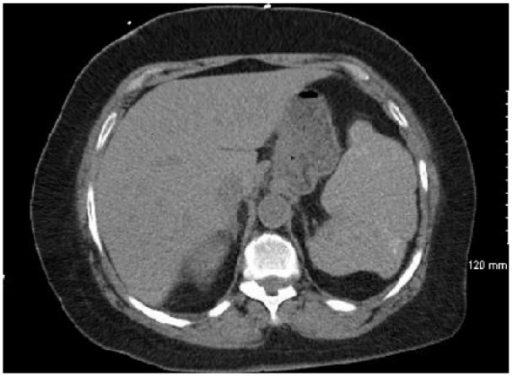

Open-I Acute Splenic Sequestration Crisis in a 70-Year-Old Patient With Hemoglobin SC Disease. Squiers JJ, Edwards AG, Parra A, Hofmann SL - Journal of investigative medicine high impact case reports (2016)